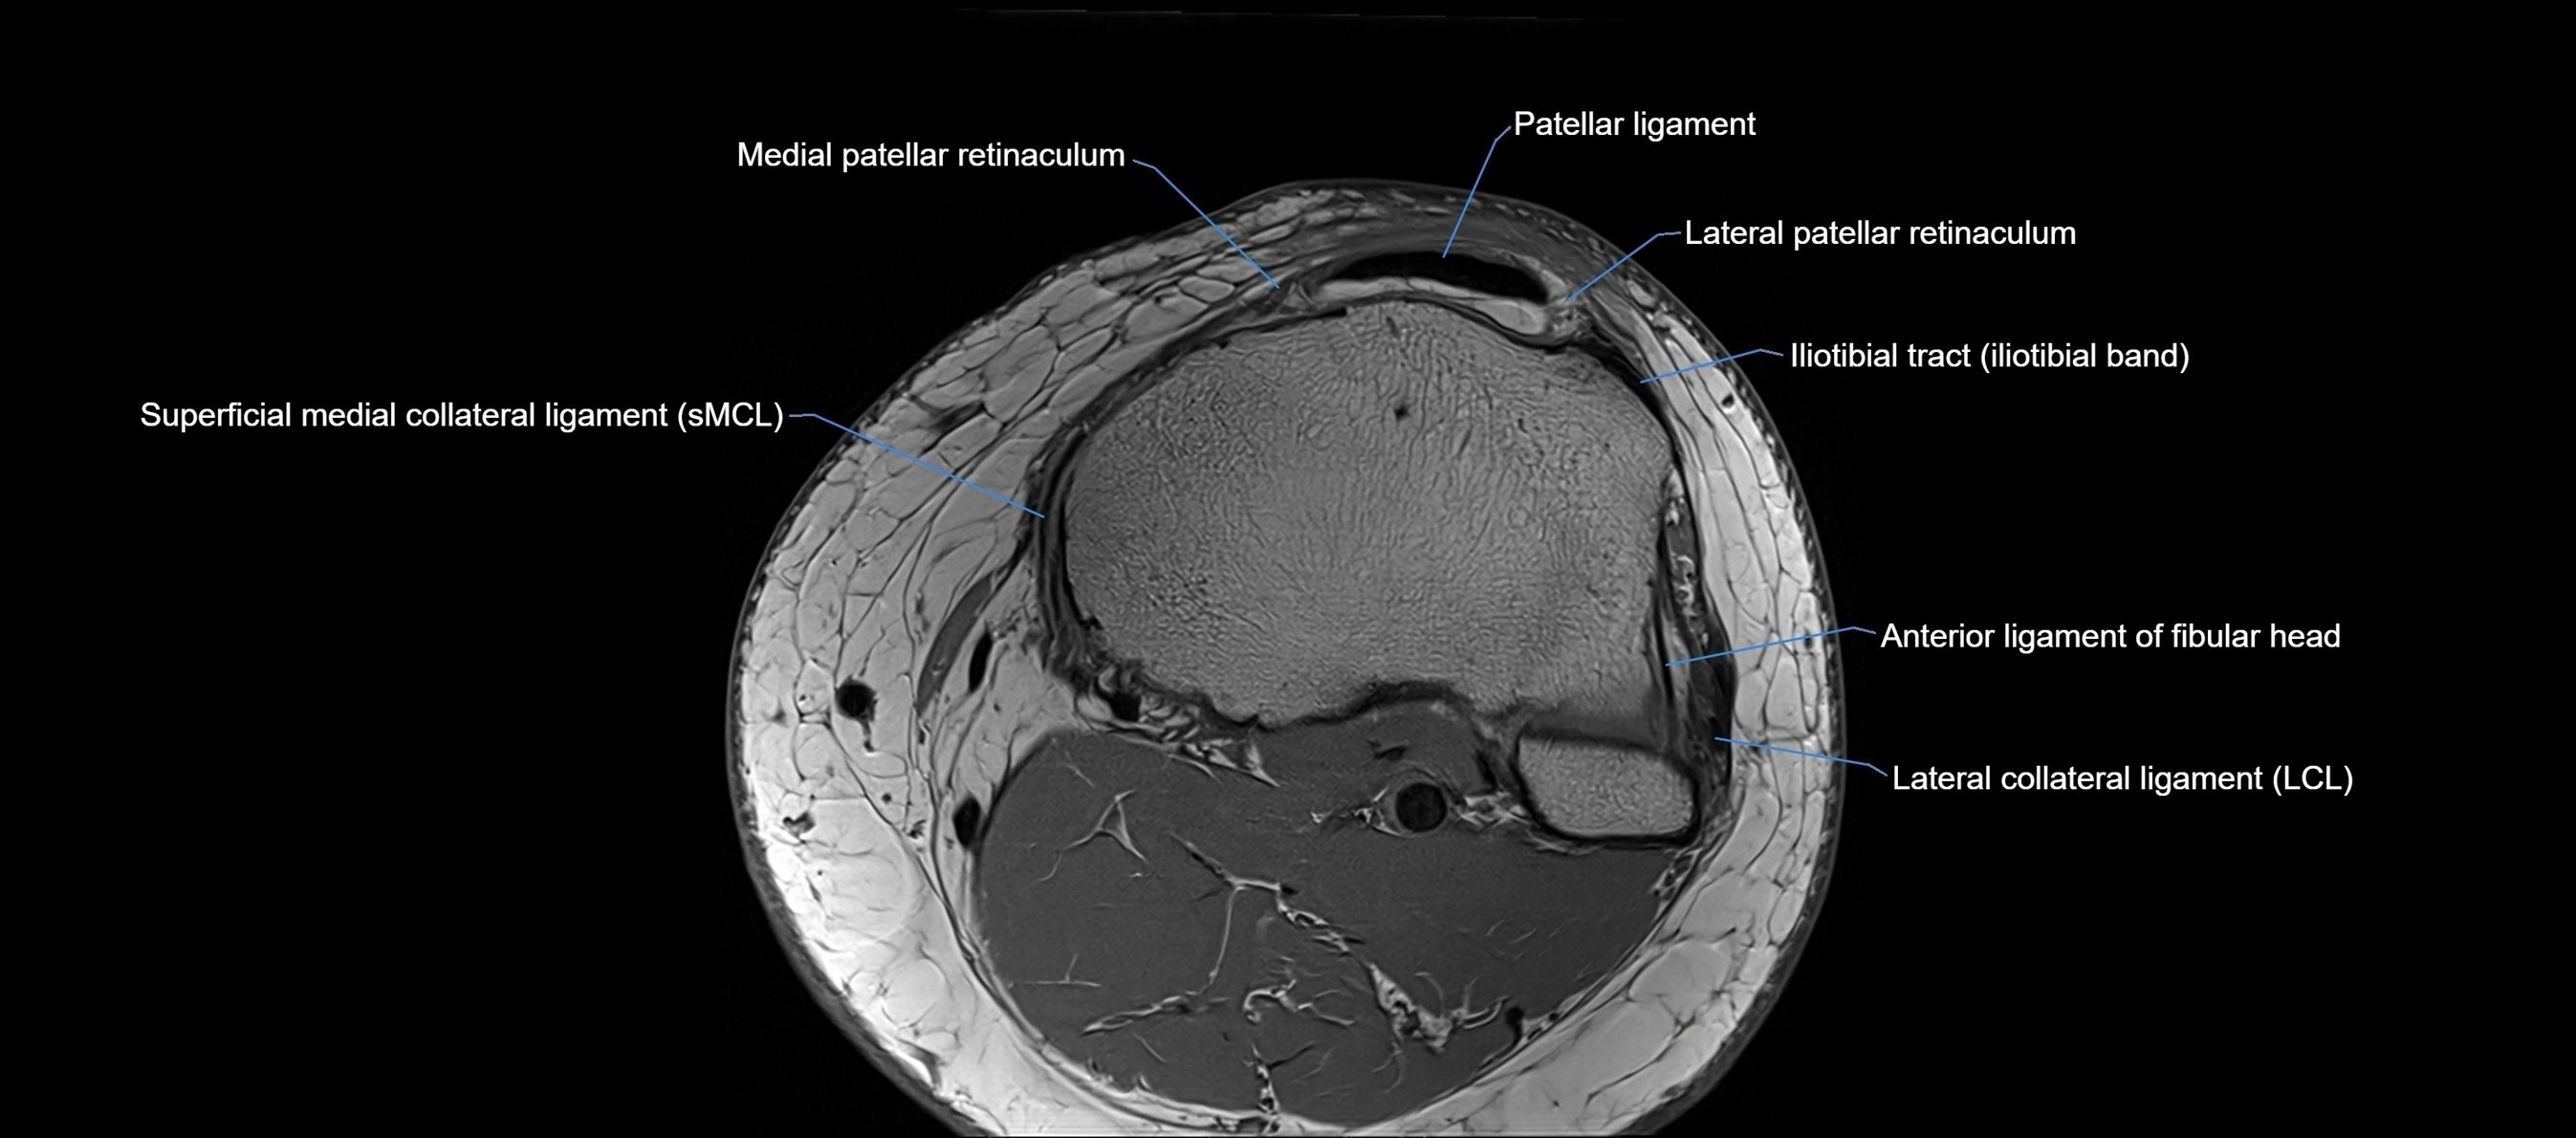

MRI images

image